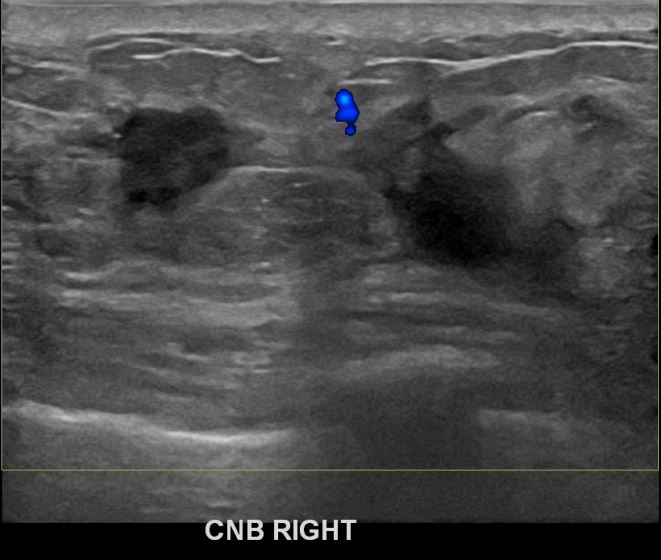

아산유외과개원후 706번째 유방암진단

상기환자 건진상 이상소견으로 조직검사권유받고 내원하신 40대 여성분으로 우측유방멍울 조직검사시행후 유방암 진단되었습니다